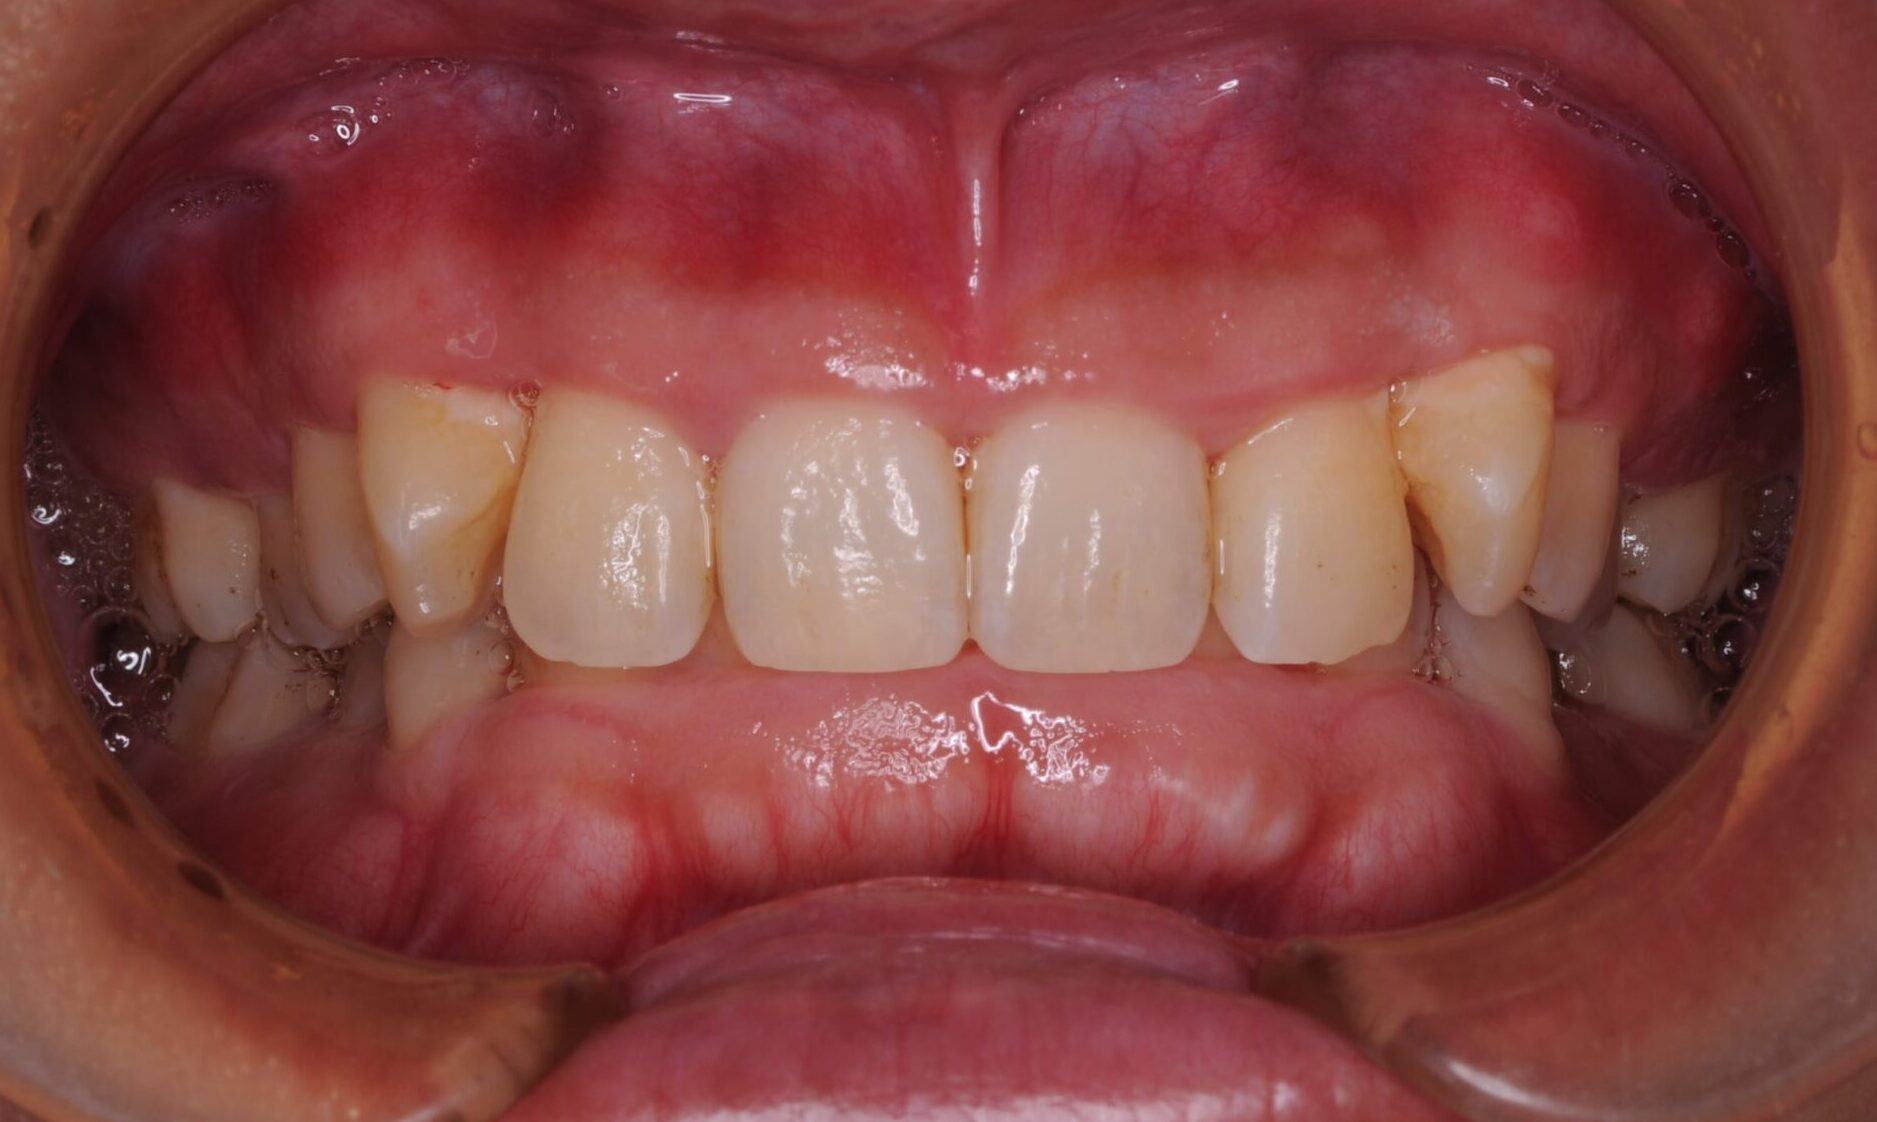

症例写真 after